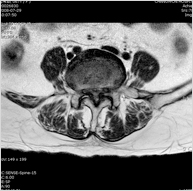

척추협착증

척추신경은 척추관을 통하여 머리부터 꼬리뼈까지 내려오는데 여러 가지 원인에 의해 신경이 다니는 길이 좁아져 신경이 압박되고 또한 신경으로 가는 혈관이 눌리게 되어 신경으로 혈액이 제대로 공급되어지지 않아 증상이 나타나는 것으로 주로 조금만 걸으면 다리가 무지근하게 아프거나 힘이 없어져서 많이 걷기가 힘들어 진다.

원인

디스크와 신경관 주위 조직이 두꺼워져 척추관이 좁아진다.

척추협착증 - 사진

치료

• 비수술적치료: 증상이 심하지 않은 경우는 약물치료, 운동치료, 신경치료 등으로 증상을 완화시킬 수 있다.

• 수술적치료: 증상이 심하여 수술이 꼭 필요한 경우 나이와 효과 등을 고려하여 미세현미경적 신경 감압술 등의 치료를 할 수가 있다.